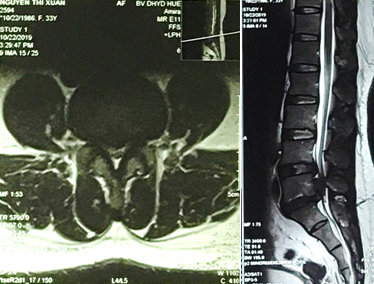

Hình 3. MRI thoát vị đĩa đệm di trú trên tầng L5/S1, chèn ép bao màng cứng và rễ thần kinh tương ứng. Lồi đĩa đệm ra sau L4/L5.

Khi khám thực thể, bệnh nhân đã tỉnh táo và định hướng và có dấu hiệu sinh tồn ổn định. Thử nghiệm Lasegue dương tính 30 độ cả hai chân, cơ lực tốt trong tất cả các nhóm cơ của chi dưới bên phải. Sức cơ của chi dưới bên trái đã giảm xuống còn 3 trên 5 trong các cơ hamstrings, và cơ tứ đầu đùi; 2-3 trên 5 (theo ASIA) trong các cơ bắp chân và duỗi ngón cái dài, ngắn. Phản xạ gân xương cho thấy bình thường phản xạ gân xương bánh chè, giảm phản xạ gân Achilles hai bên. Khám cảm giác: dị cảm khu vực quanh hậu môn. Phản xạ cơ thắt hậu môn đã giảm. X quang cột sống thắt lưng cho thấy hẹp nhẹ của các khoảng gian đốt sống L4/L5, L5/S1. Cộng hưởng từ (MRI) của thắt lưng cột sống cho thấy thoát vị đĩa đệm di trú trên tầng L5/S1, chèn ép bao màng cứng và rễ thần kinh tương ứng. Lồi đĩa đệm ra sau L4/L5, chèn ép bao màng cứng và rễ thần kinh tương ứng (Hình 3). Bệnh nhân được chẩn đoán thoát vị đĩa đệm L4/L5, L5/ S1 gây hội chứng chùm đuôi ngựa và được phẫu thuật cấp cứu. Phẫu thuật mở bản sống L4/l5, L5/S1 giải áp rộng rãi kèm cố định cột sống bằng vít qua cuống (Hình 4). Hậu phẫu, không có biến chứng gì, thiếu hụt cảm giác và vận động cải thiện; bệnh nhân vẫn giảm trương lực cơ thắt hậu môn và chưa có cảm giác đi tiểu lại. Bệnh nhân được chuyển đến đơn vị phục hồi chức năng cho trị liệu tiếp tục và hướng dẫn bệnh nhân đặt thông tiêu ngắt quãng. Hai tháng sau phẫu thuật, bệnh nhân đã có thể đi lại bình thường, mặc dù dáng đi rộng và chậm. Cảm giác đi tiểu và đại tiện cải thiện đáng kể 3 tháng sau phẫu thuật.